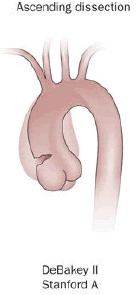

Aortic Dissection

Aortic dissection is caused by shearing force allowing blood leaking through the media of the aortic wall due to an intimal tear.

Aortic dissection occurs in the high-stress zone of the proximal portion of the aorta and is accompanied by medial weakening.

Risk factors of aortic dissection include:

- Hypertension in elderly persons, characterized by vasa vasorum hyaline arteriosclerosis

- Genetic connective tissue abnormalities in younger individuals such as Marfan syndrome or Ehlers-Danlos syndrome, characterized by weak connective tissue and cystic medial degeneration

The media sags as a result of decreased flow.

Weakness of the connective tissue in the media is a characteristic symptom of Marfan syndrome and Ehlers-Danlos syndrome (cystic medial necrosis).

Symptoms of aortic dissection include:

- Intense chest pain

- Chest pain that radiates to the back

Complications of aortic dissection include:

- Death secondary to cardiac tamponade (the most common)

- Rupture with lethal hemorrhage

- Obstruction of branching arteries (such as the coronary or renal arteries)

- End-organ ischemia